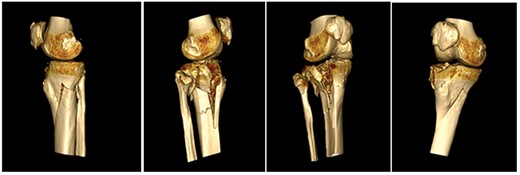

A 68-year-old gentleman who was diagnosed with a Schatzker type VI fracture having fallen 3 m from a ladder (Figs 1 and 2). The injury was closed and neurovascularly intact. The patient was monitored for signs of compartment syndrome. He rapidly developed significant fracture blisters that persisted for over 2 weeks despite regular dressing care. He was deemed too high risk for acute operative intervention because of a high risk of wound complications. Following a multidisciplinary team discussion, he was managed in a cast then a knee brace, mobilising non weight bearing for 12 weeks, at which point the fracture was seen to be healing in a valgus malalignment. The patient was allowed to partially weight bear and received physiotherapy. He was reviewed regularly until fracture had united (Fig. 3). At 8 months post-injury, the patient underwent total knee arthroplasty utilizing a Depuy Synthes (Warsaw, In) PFC Sigma TC3 tibial metaphyseal sleeve and stem, and femoral component without sleeve or stem (Fig. 4). The patient was reviewed post-operatively in clinic at 6 months, the wound had fully healed and the range of motion was 0°–120°. The patient’s pain was significantly reduced, and they were independently mobile. They were kept under annual review and seen at 5 years post-operatively with an Oxford Knee score of 35; the patient used no walking aids and was pain free at rest or during normal walking, with the radiograph demonstrating good osseointegration. The latest follow-up at 8 years revealed no radiographical change in implant (Fig. 5).